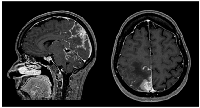

Figure 2

Neuraxis MRI at BM and LMC initial moment of diagnosis.

Disseminated LMC (extended to cerebellar fissures, midbrain, brachiocephalic bridge and cranial nerves emergence).

Sixteen months later (1.3 years), the patient was admitted to the emergency department with severe right headache (only mild response to pain medication and presence of other red flags: vomiting, night awakening, neurological deficits - visual deficits, facial paresthesias, dizziness; vertigo and decreased left upper limb muscular strength). Cranioencephalic computed tomography (CE-CT) showed a heterogeneous space-occupying lesion, in the right posterior parietal-parasagittal cortico-subcortical area, with vasogenic edema and sulcal effacement, compatible with a new BM lesion. Cranioencephalic magnetic resonance imaging (CE-MRI) confirmed the lesion genesis, showing new pachymeningeal carcinomatosis (right next to the lesion) and disseminated leptomeningeal carcinomatosis (LMC) (extended to cerebellar fissures, midbrain and brachiocephalic bridge, involving the cranial nerves emergence as well) (Figure 1). An important mass effect was present, compressing and occluding the right vertebral artery V4 terminal segment. Neuraxis MRI confirmed disseminated LMC in all neuraxis (extension to the conus medullaris limit) (Figure 2). Lumbar puncture showed a turbid cerebrospinal fluid (CSF), with cytology demonstrating small, scattered lymphocytes, large epithelial cells exhibiting irregular, hyperchromatic nuclei, and the presence of the ‘cell-in-cell’ phenomenon. The fluid was histologically confirmed as central nervous system (CNS) metastasis of HER2 positive BC. Re-staging showed neither local nor distant disease.